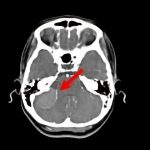

断層撮影

手術前1

手術前2